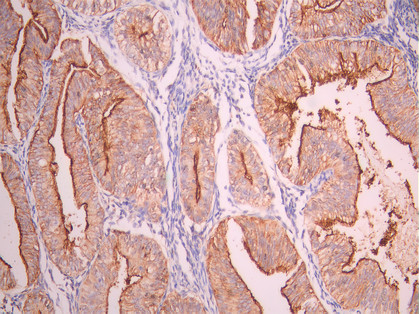

IHC image of CSB-RA192672A0HU diluted at 1:100 and staining in paraffin-embedded human salivary gland tissue performed on a Leica BondTM system. After dewaxing and hydration, antigen retrieval was mediated by high pressure in a citrate buffer (pH 6.0). Section was blocked with 10% normal goat serum 30min at RT. Then primary antibody (1% BSA) was incubated at 4°C overnight. The primary is detected by a Goat anti-rabbit polymer IgG labeled by HRP and visualized using 0.05% DAB.